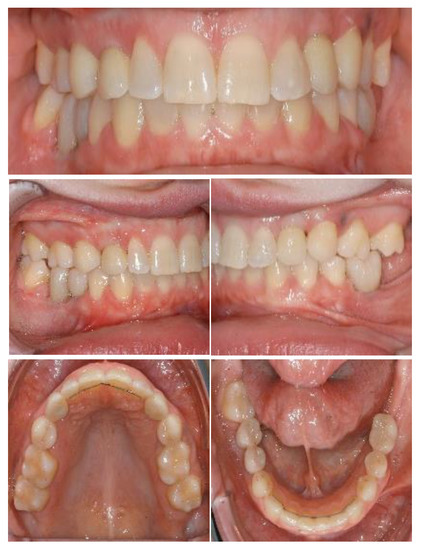

Figure 5.

Left: final orthopantomogram showing the dental implants. Right: intra-oral situation after final rehabilitation with dental-supported and implant-supported prosthesis [12].

The placement of two titanium dental implants (Bone Level 4.1 × 8 mm, Straumann) at premolar and molar sites (35, 36) was planned. Surgical procedures were conducted under local anesthesia following a healing period of three months prior to implant exposure and prosthetic rehabilitation. Figure 5 shows the final prosthodontic rehabilitation at one year follow-up. Clinical outcomes showed osseointegration of dental implants and health of peri-implant tissues.